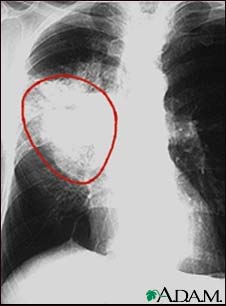

A CXR in a patient with central cancer of the right lung. Notice the white mass in the middle portion of the right lung (seen on the left side of the picture).